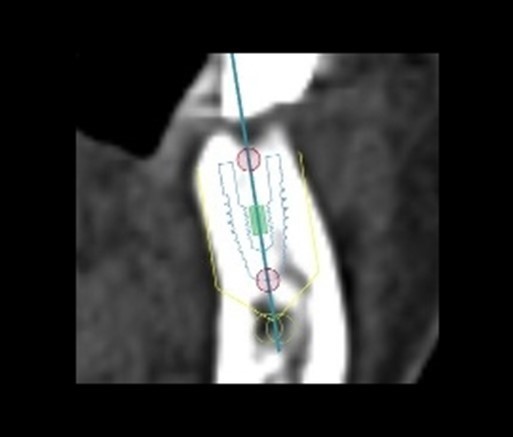

⑤ インプラント治療

インプラント治療を行う上で重要な骨の量・骨の密度がCTにより正確に算出され、治療の成功率は飛躍的に向上します。

またインプラントの埋入量や方向なども的確にシミュレートされるので、CT撮影なしで行う手術に比べ安全性も格段に向上します。